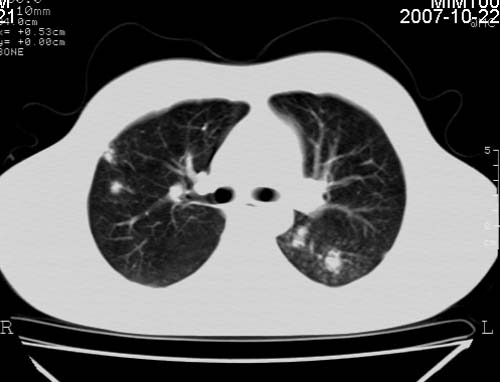

男,21岁,咳嗽、胸闷、乏力伴多汗二十余日、无明显发烧。患者一般情况好,为初三学生。

右肺上叶前段及左肺下叶多形性病变伴厚壁空洞,周边示树芽征.左肺下叶不张改变.

考虑;肺结核,不除外左肺下叶支气管内膜结核.

双肺继发性肺结核伴左侧空洞形成!不除外合并霉菌感染!(双肺多发病灶,左侧病灶形成空洞,并空洞内见壁结节。建议改变体位,观察空洞内结节情况,以便排除霉菌感染!)